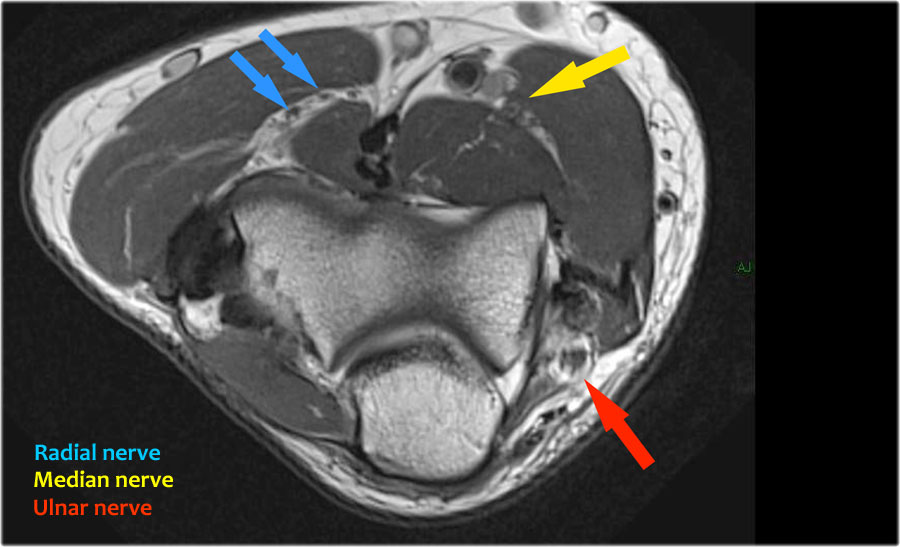

Radial nerve

Dây thần kinh quay có thể được xác định rõ nhất ở mức chỏm xương quay, nơi có thể quan sát thấy các nhánh nông và nhánh sâu trong ống xương quay (mũi tên).

This is a very consistent place to find the radial nerve.

Các nhánh quay sâu tạo thành thần kinh gian cốt sau xuyên qua cơ ngửa tại cung Frohse (mũi tên).